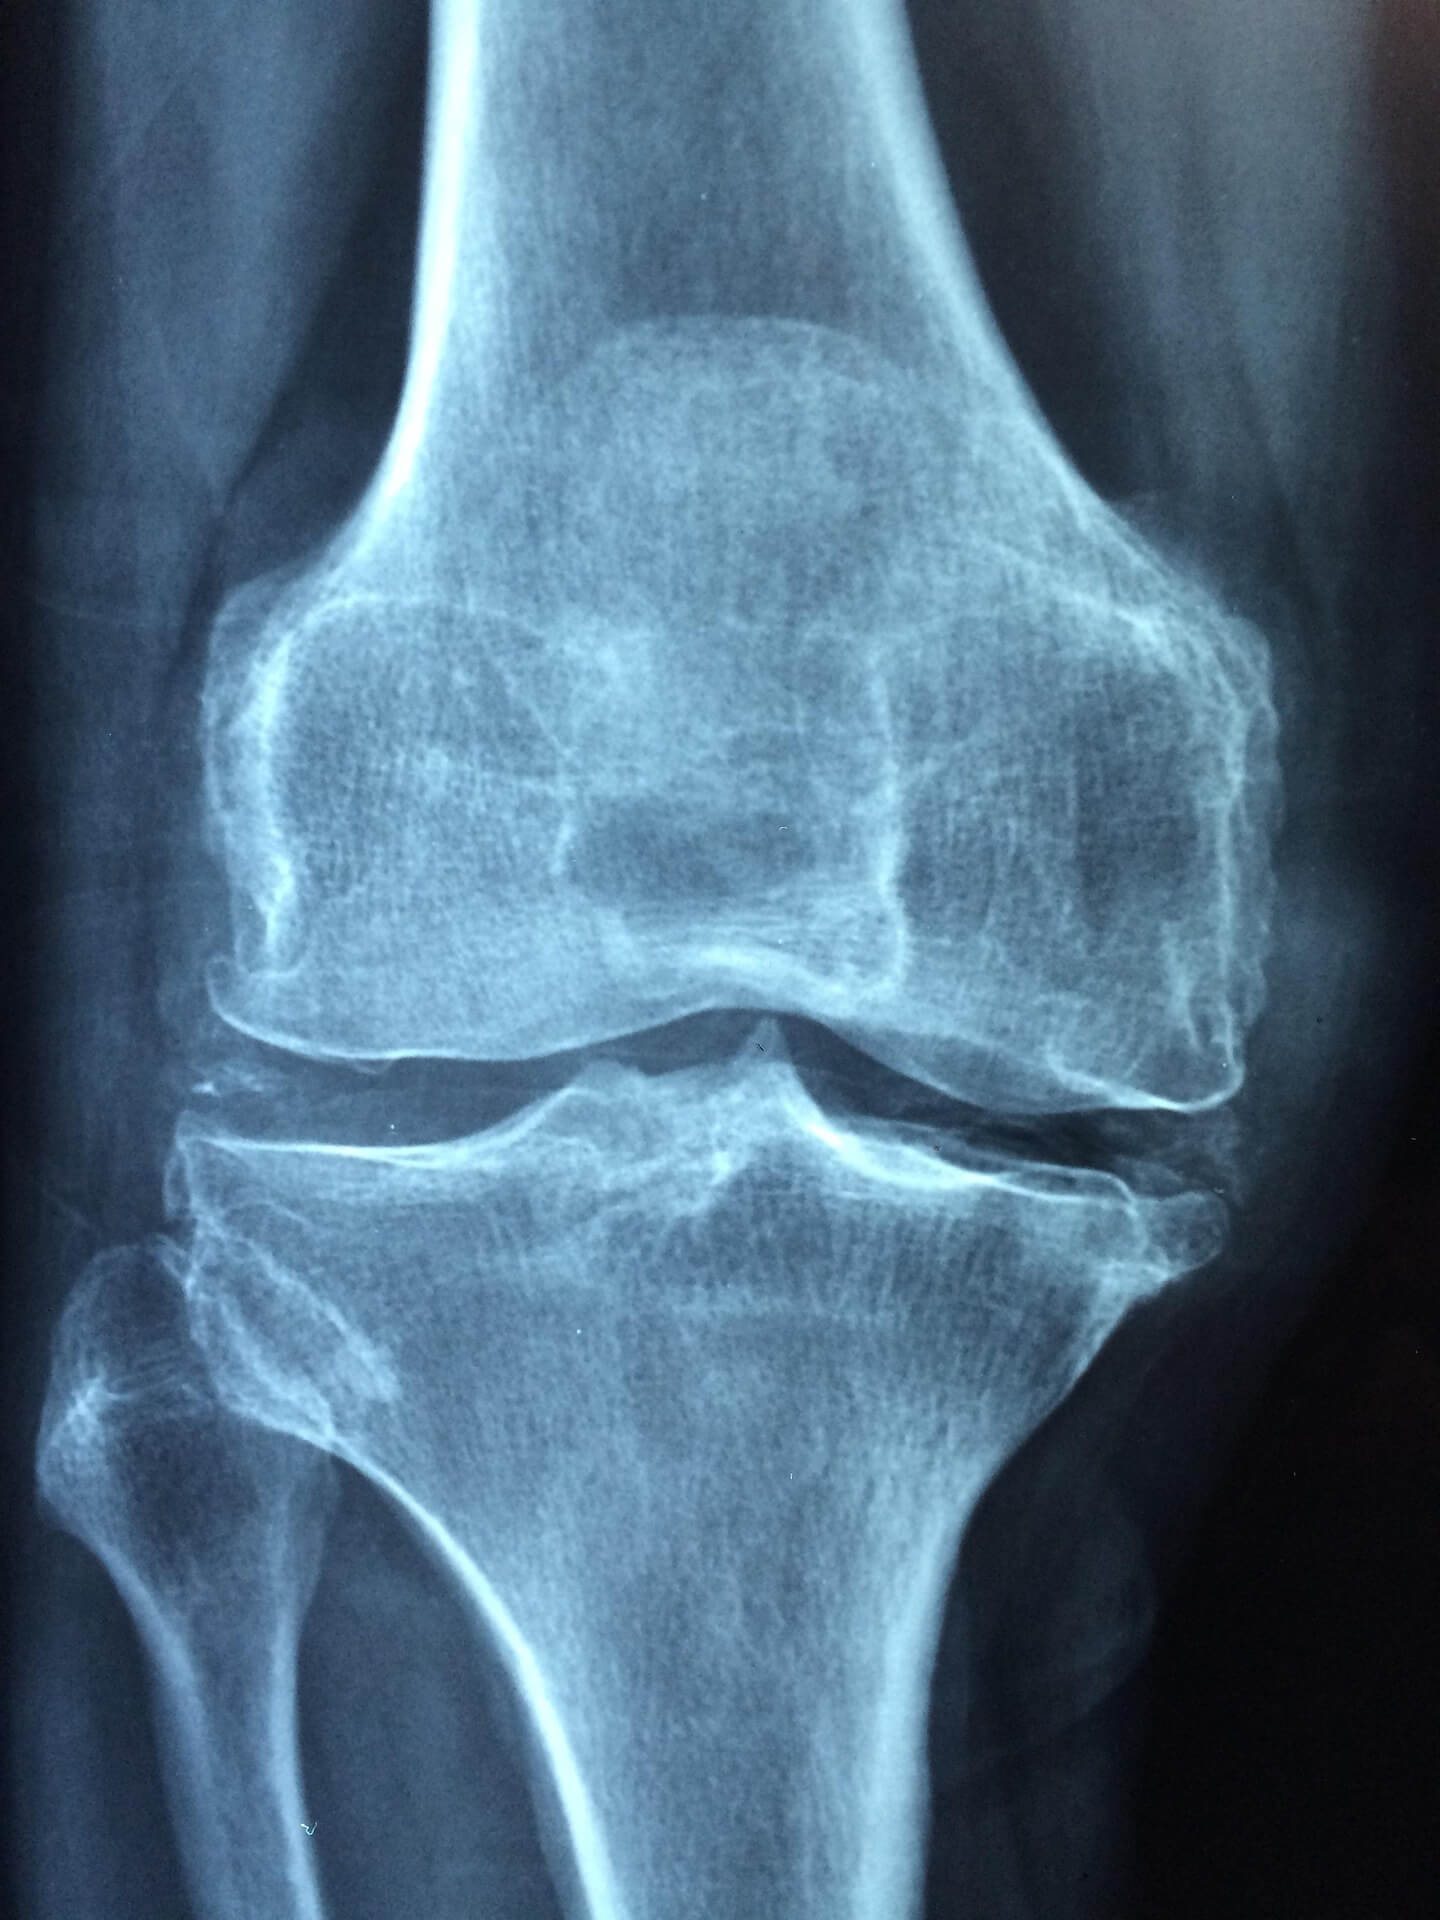

골밀도 검사는 X-ray나 초음파로 진행됩니다. T-score가 -1.0 이하라면 주의 단계, -2.5 이하라면 골다공증으로 진단됩니다. 조기 진단을 위해 1년에 한 번 검사를 권장합니다.

최근에는 AI가 X-ray 이미지를 분석해 골다공증 위험을 조기에 예측하는 연구가 활발히 진행되고 있습니다. 이는 독일과 미국에서 50세 이상 여성을 대상으로 실시한 결과, 기존 검사보다 정확도가 높았습니다.